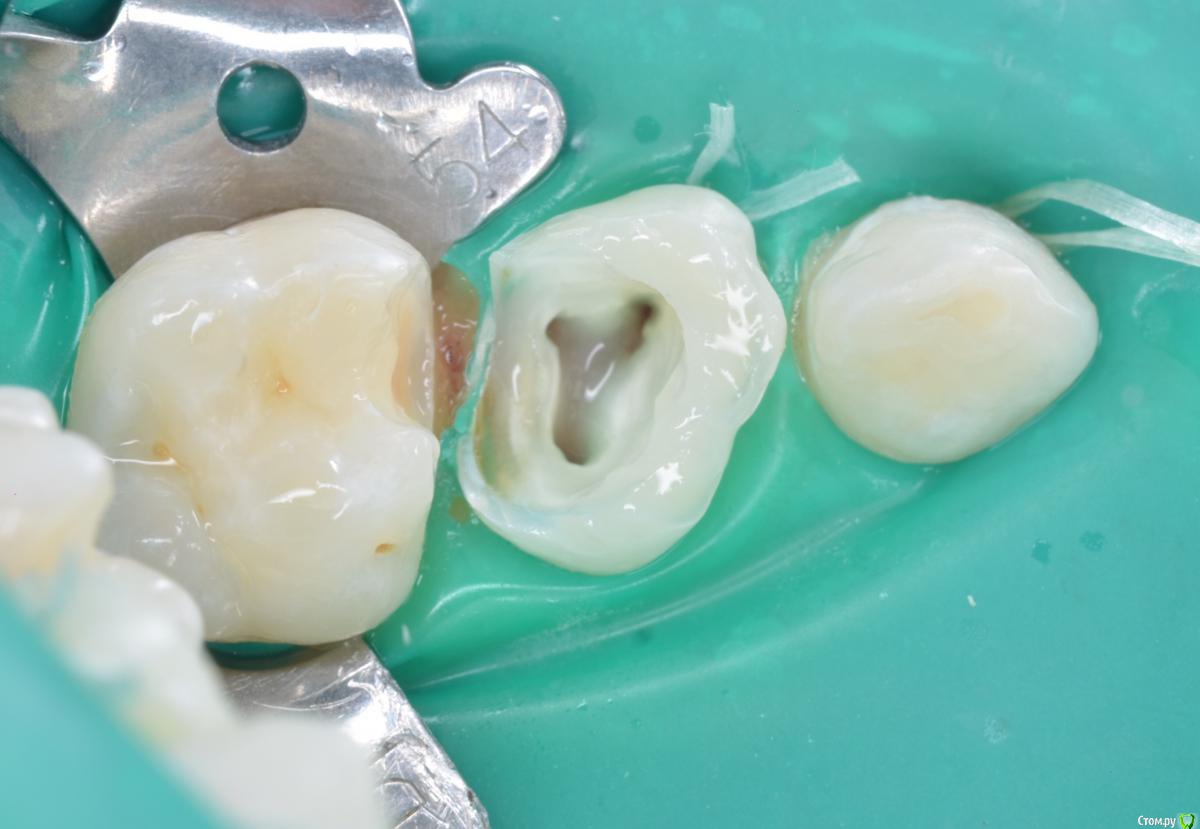

CRAZYDUCK Опубликовано 15 мая, 2018 Автор Поделиться Опубликовано 15 мая, 2018 Гипоплазия и кариес 3.6 . Анестезия инфильтрация плюс проводниковая ( точнее «плавная» проводниковая )Акцентируем внимание родителей , что десна будет беспокоить некоторое время ( но это индивидуально ).Кариес маркер использую больше для наглядности ( когда показываю фото родителям). 1 Ссылка на комментарий

CRAZYDUCK Опубликовано 19 мая, 2018 Автор Поделиться Опубликовано 19 мая, 2018 (изменено) Костя , 7 лет .Лечение кариеса 1.6; обратимый пульпит 5.4 и 5.5 .5.4 заполирован по контакту после снятия коффера, платок два раза меняла ( порвала по каоьакту). Фото после снятия коффердама уже не было сил сделать ;( ( новая ассистент, еще не сработались - дольше все делаем , чем с другим ассистентом .Ещё прийдет на лечение - сделаю . Изменено 19 мая, 2018 пользователем CRAZYDUCK 3 Ссылка на комментарий